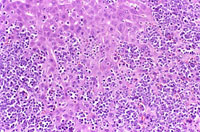

The liver is a relatively frequent site of infiltration by malignant lymphocytes, especially in strains with a high prevalence of lymphoma.

Infiltration of malignant lymphocytes in a liver from an adult mouse.

Severe infiltration of the liver by malignant lymphocytes. Hepatocytes visible in the lower right corner.